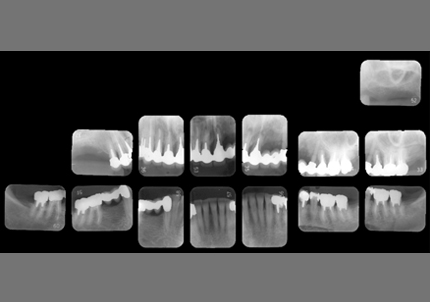

24.パノラマレントゲン

↑2006年4月24日(初診時)

↑2024年6月26日

25.初診より18年経過(2024年6月26日)